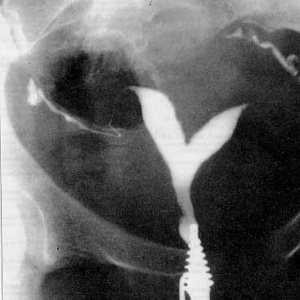

צילום רנטגן של הרחם נועד להדגמת מבנה חלל הרחם ולאבחון הידבקויות תוך רחמיות. הוא נעשה על ידי הזרקת חומר אטום לקרני רנטגן לחלל הרחם ועל ידי כך מתאר את מבנה חלל הרחם. פגמי מילוי של חומר הצבע הזה מעידים על הידבקויות תוך רחמיות. צואר רחם רחב מאד מעיד על אי ספיקה של צואר הרחם.

היסטרוסקופיה היא פעולה שבה מוחדר לחלל הרחם מיכשור אופטי זעיר ובעזרתו מצלמים את חלל הרחם וכך ניתן לאבחן רחם עם מחיצה או הדבקויות תוך רחמיות. את אלו, האחרונות, ניתן גם להסיר בזמן ההיסטרוסקופיה.